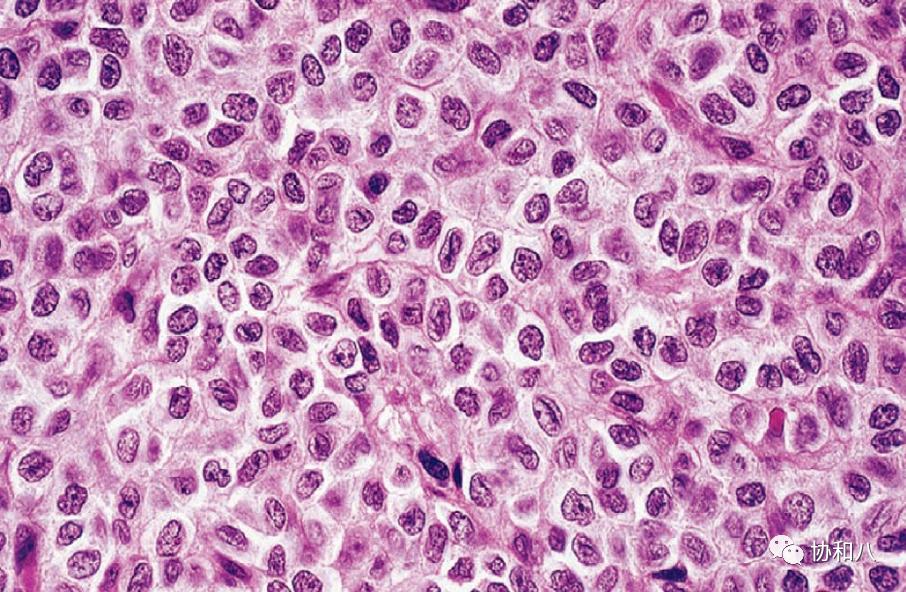

16. 爆米花细胞popcorn cell:

又称Reed-Sternberg(RS)细胞,见于淋巴细胞为主型霍奇金淋巴瘤,这种多核细胞的形态特点为细胞体积大,胞核皱折、多分叶状,染色质稀少,有多个小的嗜碱性核仁,胞浆淡染,B淋巴细胞标志物CD20阳性。